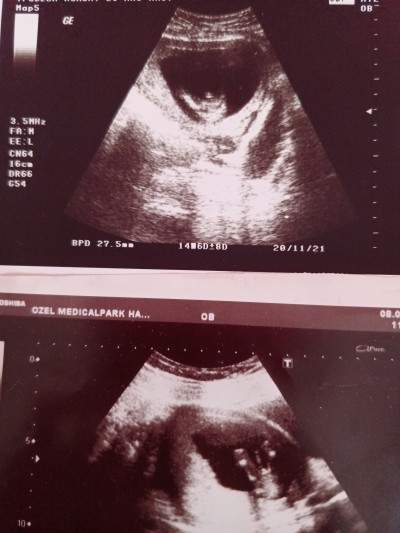

Kızlar bişey sorcam size.ben geçen hafta kontrole gittim doktor cinsiyet ile alakalı son anda gördüm sanki dedi erkek gibi dedi.sizce yanılma payı varmıdır.kesinmi diye sorunca yüzde 90 dedi ve üstüne cinsiyet için aslında 2 hafta sonra gelmen gerekli dedi ve elime bu kağıdı verdi.alttaki resim ilk oğluma ait resim üstteki ise şimdiki hamileliğim sizce erkek mi bebek.yanyana koyunca ilk bebeğimin ki çok net belli ama bu verdiği resim bi tuhaf geldi o bacaksa öbürü nerde anlamadım

image

Gebelik haftası 16